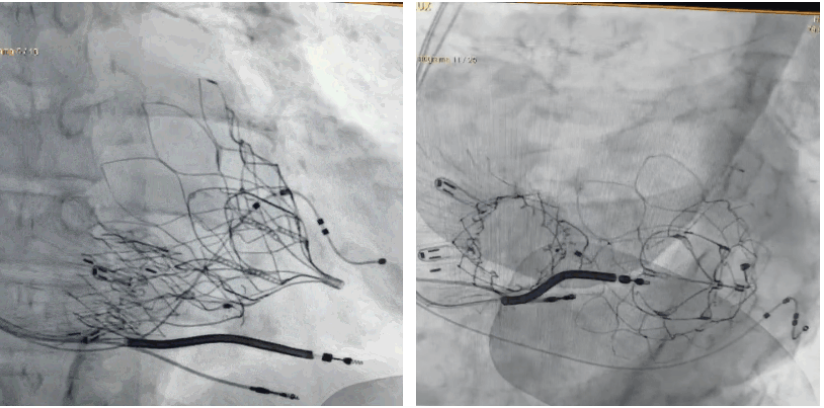

術后DSA顯示Lux-Valve Plus與Tendyne和ICD無相互影響

手術在全麻狀態(tài)下進行。術者采用經(jīng)右側頸靜脈入路的方式將輸送器送入患者心臟內(nèi),在TEE及DSA引導下調(diào)整輸送器頭端角度,使得輸送器與三尖瓣瓣環(huán)平面垂直。在輸送器進入右心室后釋放室間隔錨定裝置,而后釋放瓣葉夾持件(2個耳片結構)成垂直狀態(tài)。在TEE及DSA確定夾持件固定至三尖瓣葉根部且位于右室側后釋放人工瓣心房側盤片。隨后調(diào)整瓣膜同軸性以及室間隔錨定件位置(貼合室間隔),前推藏針管并固定,進而釋放室間隔錨定裝置,并再次確認瓣膜位置、穩(wěn)定性及同軸性,合攏輸送鞘后撤出輸送器,完成LuX-Valve Plus人工三尖瓣瓣膜的植入,僅殘余微量瓣周漏。且經(jīng)手術中心電生理團隊評估,病人的起搏器和ICD功能沒有受到影響。